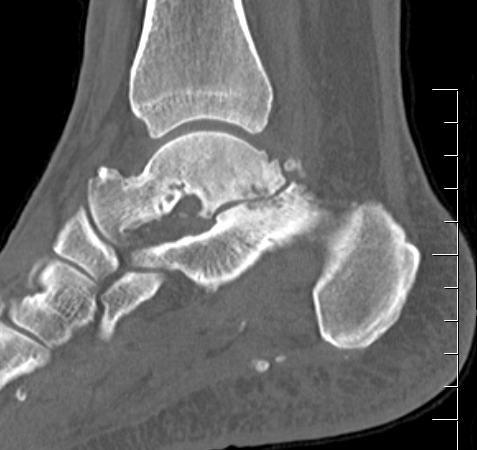

CT

Subluxation of TNJ with advanced STJ OA

TNJ OA with posterior / medial / anterior facet OA of the subtalar joint